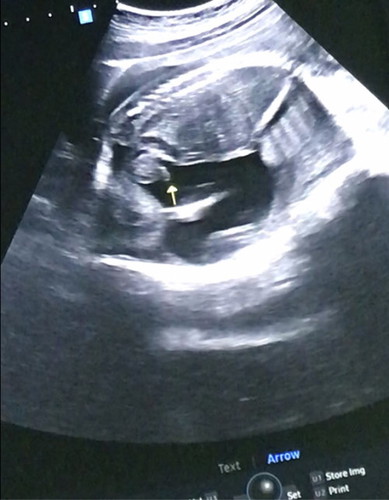

บ้านนี้ตอนไปซาวน้องอายุครรภ์ประมาณ20+2น้ำหนักน้อง717เยอะไปมั้ยคะเเม่ๆกังวลจังเลยค่ะน้องเป็นเพศชายค่ะในจอซาวก็ตัวใหญ่มากเลยค่ะเเต่ท้องหนูเล็กมากๆตอนนี้ปัจจุบัน23วีคเเล้วค่ะวันที่18หมอนัดอีกจะรอดูว่าน้ำหนักน้องเพื่มอีกมั้ยกลัวจังเลยค่ะเเต่หมอไม่ได้พูดอะไรนะคะแต่หนูกังวลไปเองเพราะเด็กทั่วไปเขาน่าจะ300-400กรัมมั้ยคะอายุครรช่วง5-6เดือนเเบบหนูจากที่หนูอ่านมา#ท้องเเรก